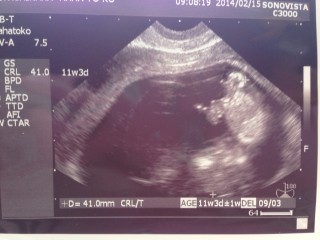

CRL 41.0mm

手を握ったり開いたり

力強くキックしたりしてました!

ちょうど右足をキックしたところですね!